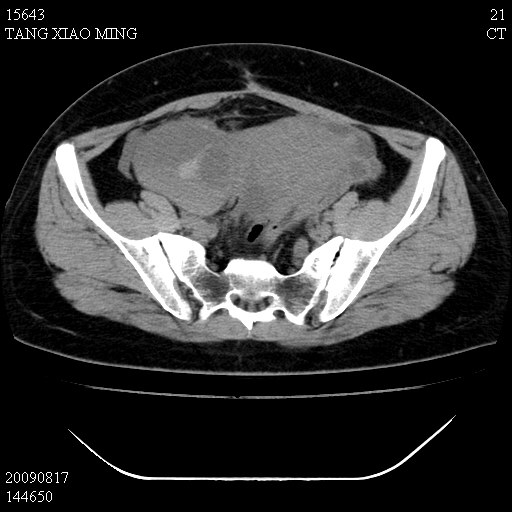

标题: CT21692:盆腔病变

女,33岁,右下腹痛2年余,既往宫外孕病史,如在我院手术,结果下周公布,

可能的诊断。1子宫内膜异位【子宫腺肌症并右卵巢巧克力囊肿】;2 右卵巢囊腺瘤。子宫肌瘤

1)考虑卵巢巧克力囊肿,不排除卵巢囊腺瘤。2)子宫肌瘤可能。

卵巢囊腺瘤,子宫肌瘤,直肠壁厚,不除外占位.